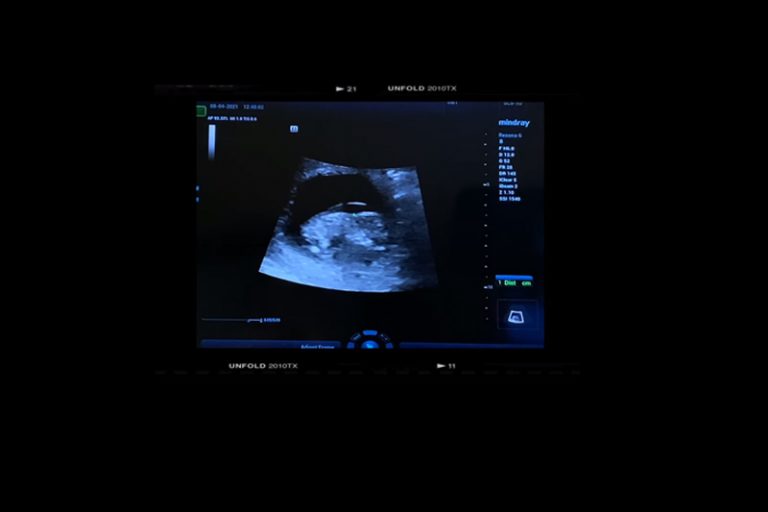

可是其後在懷孕第10周5天,Leanne接受產檢被告知胎兒的頸皮厚,醫生解釋胎兒的頸皮有5.5mm厚,需要驗血進一步檢查,有可能是唐氏綜合症或心臟出問題。Leanne稱:「聽完之後我整個人迷失了。等報告的一星期每日除了喊,就是上網看其他媽媽的經歷。跟陳生商量,如果是唐氏我們都可以接受。有能力照顧你和給你無限的愛。終於收到醫生的電話,驗血報告你沒有唐氏,但有愛德華氏症T18。我從來沒有聽過這個病。當刻完全沒有概念是什麼。只知道醫生叫我下一步抽絨毛,當上網搵資料嘅時候,我彷彿靈魂出竅,為什麼會發生我身上。愛德華氏症根本是沒有希望的病。很大部份機會胎死腹中,就算可以出世,都是得幾分鐘或者幾個鐘或者幾個月。莫非上天真的不想我擁有你?」

心碎不已的Leanne引述醫生解釋胎兒的問題,「左右腦沒有分左右,心有嚴重的問題,沒有鼻骨,腸外露,手少了一隻骨,腳也是彎的。還有很多很多問題,醫生建議不用抽絨毛。雖然已經好肯定是愛德華氏,就算不是,也是一個畸胎,有非常嚴重的問題。所以我哋最後沒有抽。」